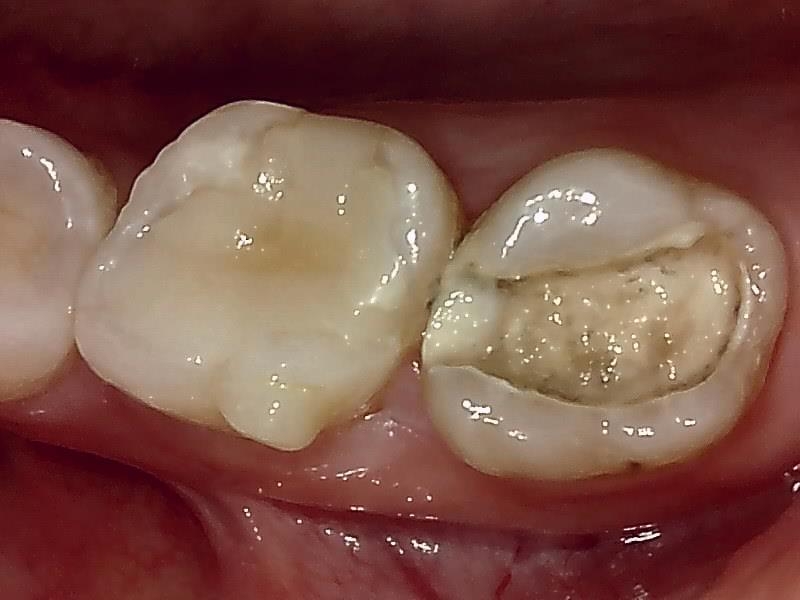

術前の写真 詰め物の脱離とカリエス